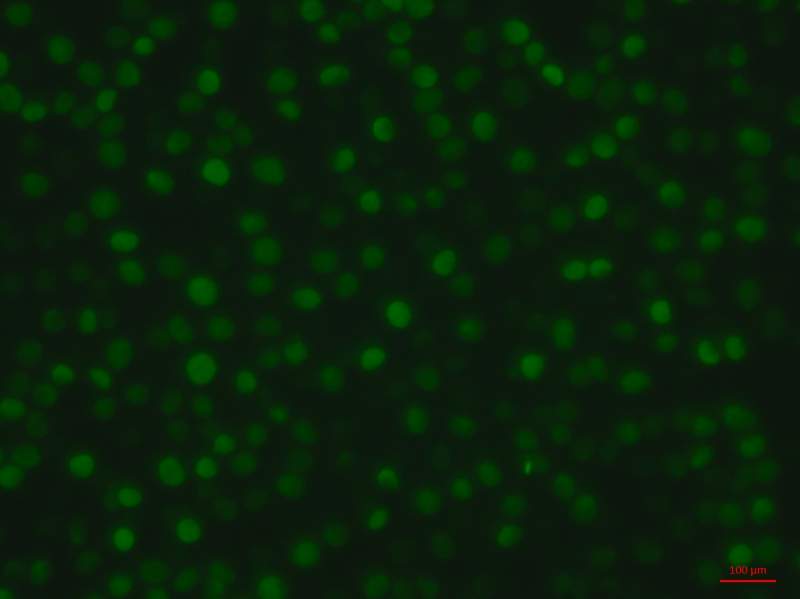

ÎÒµÄTUNELȾɫʵÑé³öÏÖµÄÎÊÌâ ÒÑÓÐ1È˲ÎÓë